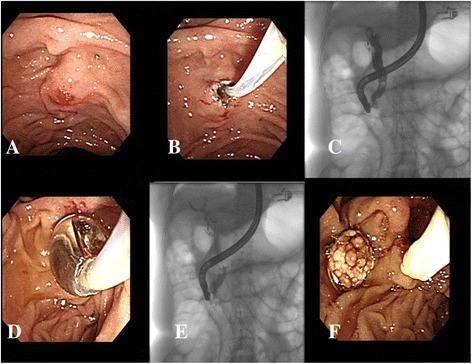

The definition of difficult biliary cannulation in our study was as follows: (1) failed cannulation within 10 min (2) 5 passages or injections of the pancreatic duct, or (3) 10 attempts at the papilla without a time limit (Fig. 1a). We stopped anticoagulant administration such as aspirin for 7 days before the procedures in those who were prescribed for primary prevention. For those who received anticoagulant for secondary prevention in low cardiovascular risk patients, we stopped clopidogrel, prasugrel, ticagrelor and coumadin 5 days before ERCP according to British Society of Gastroenterology and European Society of Gastrointestinal endoscopy [ref. 14, ref. 15]. For patients with high cardiovascular risks, the procedures were postponed if possible until anticoagulant could be discontinued safely (usually >12 months after insertion of drug-eluting coronary stents or >1 month after insertion of bare metal coronary stents). However, when an emergent or semi-emergent indication like an impacted stone or jaundice in need of immediate action was encountered, cardiologists were routinely consulted and replaced by other emergent non-endoscopic bilary driange procedures. Prophylactic NSAIDs were given to all patients to reduce risk of post-ERCP pancreatitis routinely in our department.

The patients received pharyngeal anesthesia with xylocaine spray in the same manner as that for general endoscopy. Hyoscine-N-butylbromide (20 mg) was administered intramuscularly before the procedure, and meperidine (30 to 50 mg) was administered before EPBD. ERCP was performed using a side-view endoscope (JF 260v and TJF 240; Olympus, Tokyo, Japan) after selective cannulation of the CBD with a cholangiography catheter (PR-113Q, Olympus). We preferred a needle-knife sphincterotome (KD-V441, Olympus) in all cases. Two highly experienced endoscopists [the first and second authors], with experiences of more than 3000 ERCPs procedures each, and ongoing workloads of more than 250 ERCPs procedures each annually, performed all the limited PS combined with EPBD procedures. Diathermy was applied with a blended current (20 W cut and 20 W coagulation) using the ESG 100 system (Olympus). The incision started from the lip of the papillary orifice (at the 11-o’clock position) and proceeded upward over the papillary mound. The extent of cutting in limited PS is less than half the length of the papillary mound (Fig. 1b). To perform EPBD after cannulation of the bile duct with limited PS (Fig. 1c), a 0.035-inch guide-wire (Zebra Exchange Guide-wire; Microvasive Boston Scientific, Watertown, MA) was inserted into the bile duct through the catheter. After the guide-wire was inserted deeply into the bile duct, the catheter was removed with the guide-wire left in place. A balloon-tipped catheter (5.5 cm long and 8–20 mm wide; Microvasive Boston Scientific), was inserted over the guide-wire so that the balloon was extended across the papilla. The balloon was inflated to 8–20 mm in diameter with saline solution to dilate the papilla at progressively increasing pressures of 3 to 8 atm for 2 min, according to the size of the CBD stones (Fig. 1d). After removing the dilation catheter, stones were extracted with a basket catheter or retrieval balloon (Fig. 1e, f). Endoscopic mechanical lithotripsy (EML) was used to crush stones >15 mm in diameter when extraction of these stones was difficult after EPBD. When stones were not extracted completely, a biliary stent was inserted and the residual stones were removed after 3–7 days without repeating EPBD. A prophylactic pancreatic stent was not used after EPBD. Complete stone removal was defined as the absence of bile duct stones on a balloon occlusion cholangiogram.